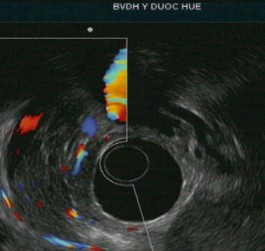

Tổn thương ống tụy: sỏi ống tụy chính, giãn ống tụy, thành của ống tụy chính không đều, tăng âm thành ống tụy chính. Nhu mô tụy thấy các nốt và dải tăng âm. Chẩn đoán chắc chắn viêm tụy mạn với tiêu chí chính A và bốn tiêu chí phụ.

Tổn thương ống tụy: ống tụy chính không giãn nhưng có tăng âm thành ống tụy. Nhu mô tụy: tổn thương dạng tổ ong, các nốt tăng âm không có bóng lưng kèm các tổn thương trống âm. Chẩn đoán nghi ngờ viêm tụy mạn với 1 tiêu chí chính B kèm 3 tiêu chí phụ.